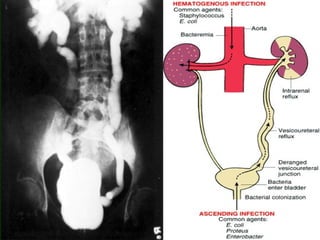

Acute pyelonephritis

 Routes of infection:

Two routes are recognized

 1- Ascending infection: this is the most

common route. Ascending infection

occur from the lower urinary tract

 2- hematogenous route; infection occur

through blood stream.